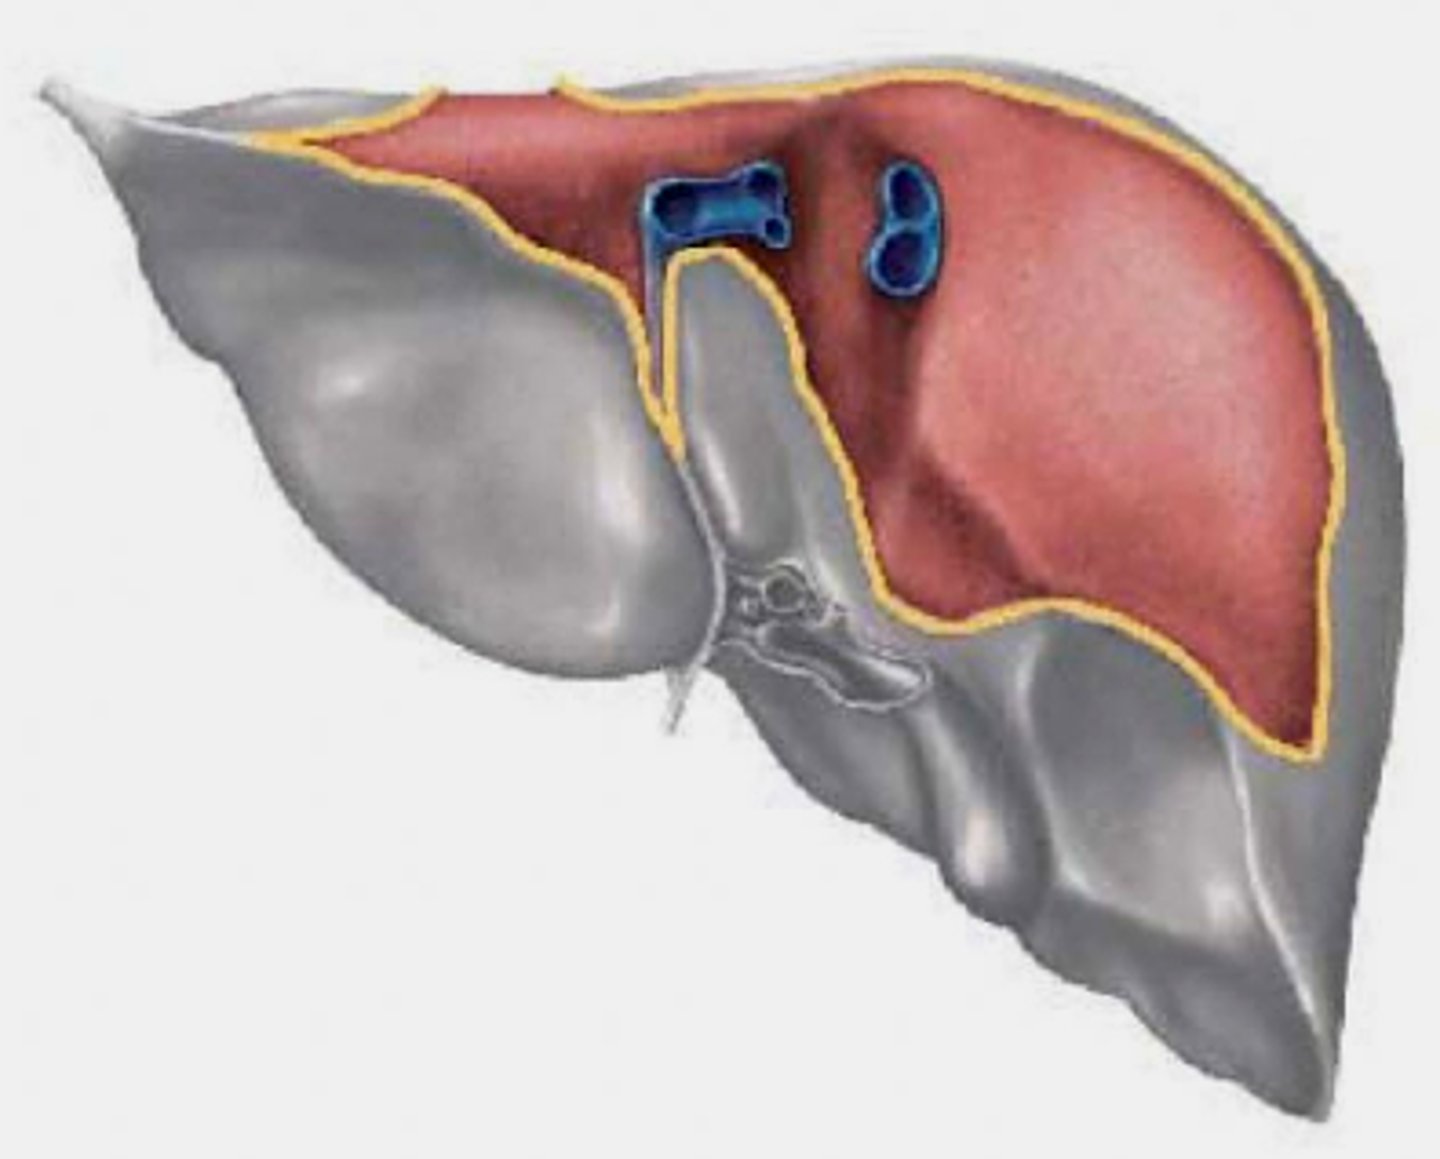

Identify the lobes of the inferior portion of the liver

knowt flashcard image

Identify the anterior lobes of the liver

Identify impressions on the inferior portion of the liver

Note that organs in direct contact with liver can spread cancer directly to the liver

<p>Note that organs in direct contact with liver can spread cancer directly to the liver</p>